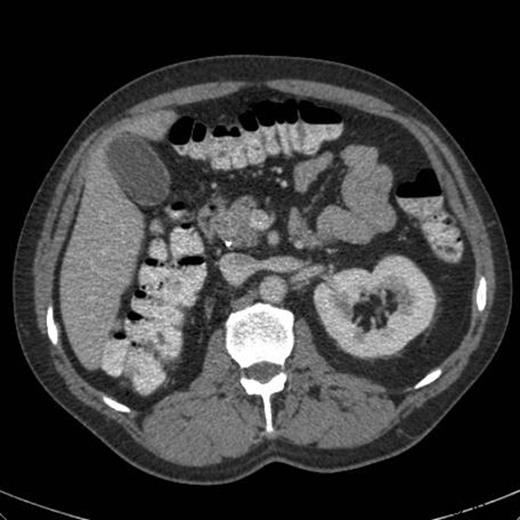

An ultrasound prior to this clinic appointment revealed a dilated Common Bile Duct (CBD) of up to 10mm, a distended thin walled gallbladder, no calculi and a normal pancreatic body. The head of the pancreas was not visualised. Laboratory tests from the GP revealed an elevated bilirubin of 150 umol/L. The CT of his abdomen and pelvis confirmed a dilated CBD and some areas of focal calcification on the head of the pancreas (Figure 3). The EUS demonstrated a thickened distal CBD with a 1.5cm hypoechoic lesion in the pancreatic head (Figure 4). The HPB MDT meeting suspected a malignant lesion and felt that a Whipple’s procedure would offer the best chance of cure.

CT abdomen demonstrating calcification at the head of the pancreas